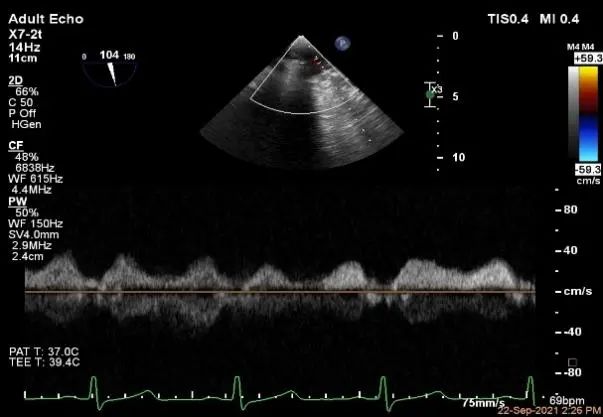

术中超声

P2区脱垂,宽14.8mm,Gap:3.3mm

3D-color,返流重度,3+级

麻醉状态下左肺静脉血流频谱

MVA:6.67cm²

肺静脉血流频谱恢复正常